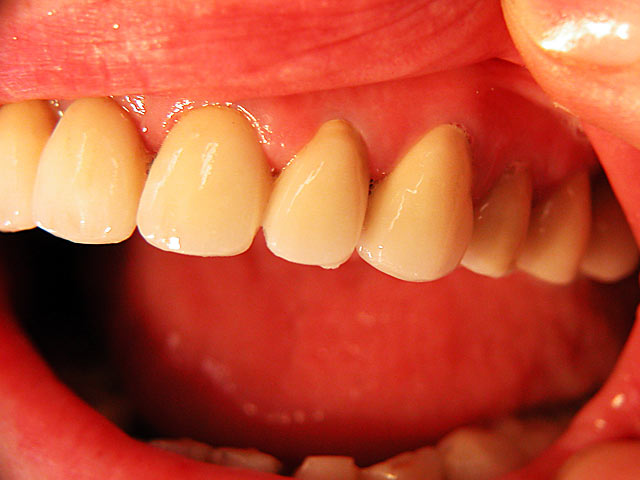

Die folgenden Patientenfälle sollen Ihnen einen Einblick in die Möglichkeiten der modernen Implantation geben.

Frontzahn-Implantation: